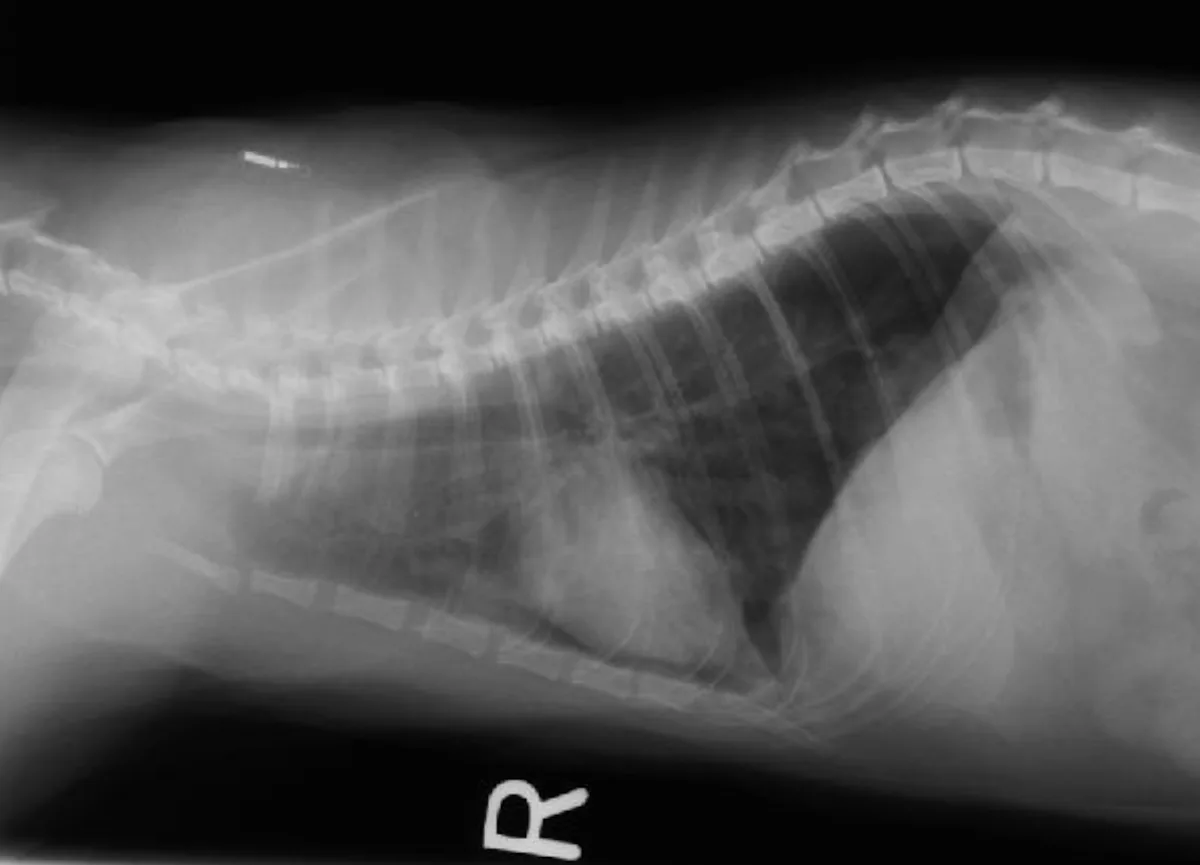

Supportive evidence of heartworm disease may be present on additional diagnostic tests. Although cats are rarely microfilaremic, microfilaria may be detected on a blood smear. Eosinophilia is often transient and rarely identified. Thoracic radiographic findings in cats with heartworm disease include enlarged pulmonary arteries, especially the right caudal lobar artery; bronchointerstitial infiltrate and occasionally pulmonary overinflation, pleural effusion, and pneumothorax may also be present. Radiographic abnormalities may be transient, and right heart enlargement is rarely identified.

Right lateral (A) and dorsoventral (B) thoracic radiographs were taken. Notice the enlarged pulmonary artery (C, arrow) in the dorsoventral view, which provided a clue to her diagnosis.